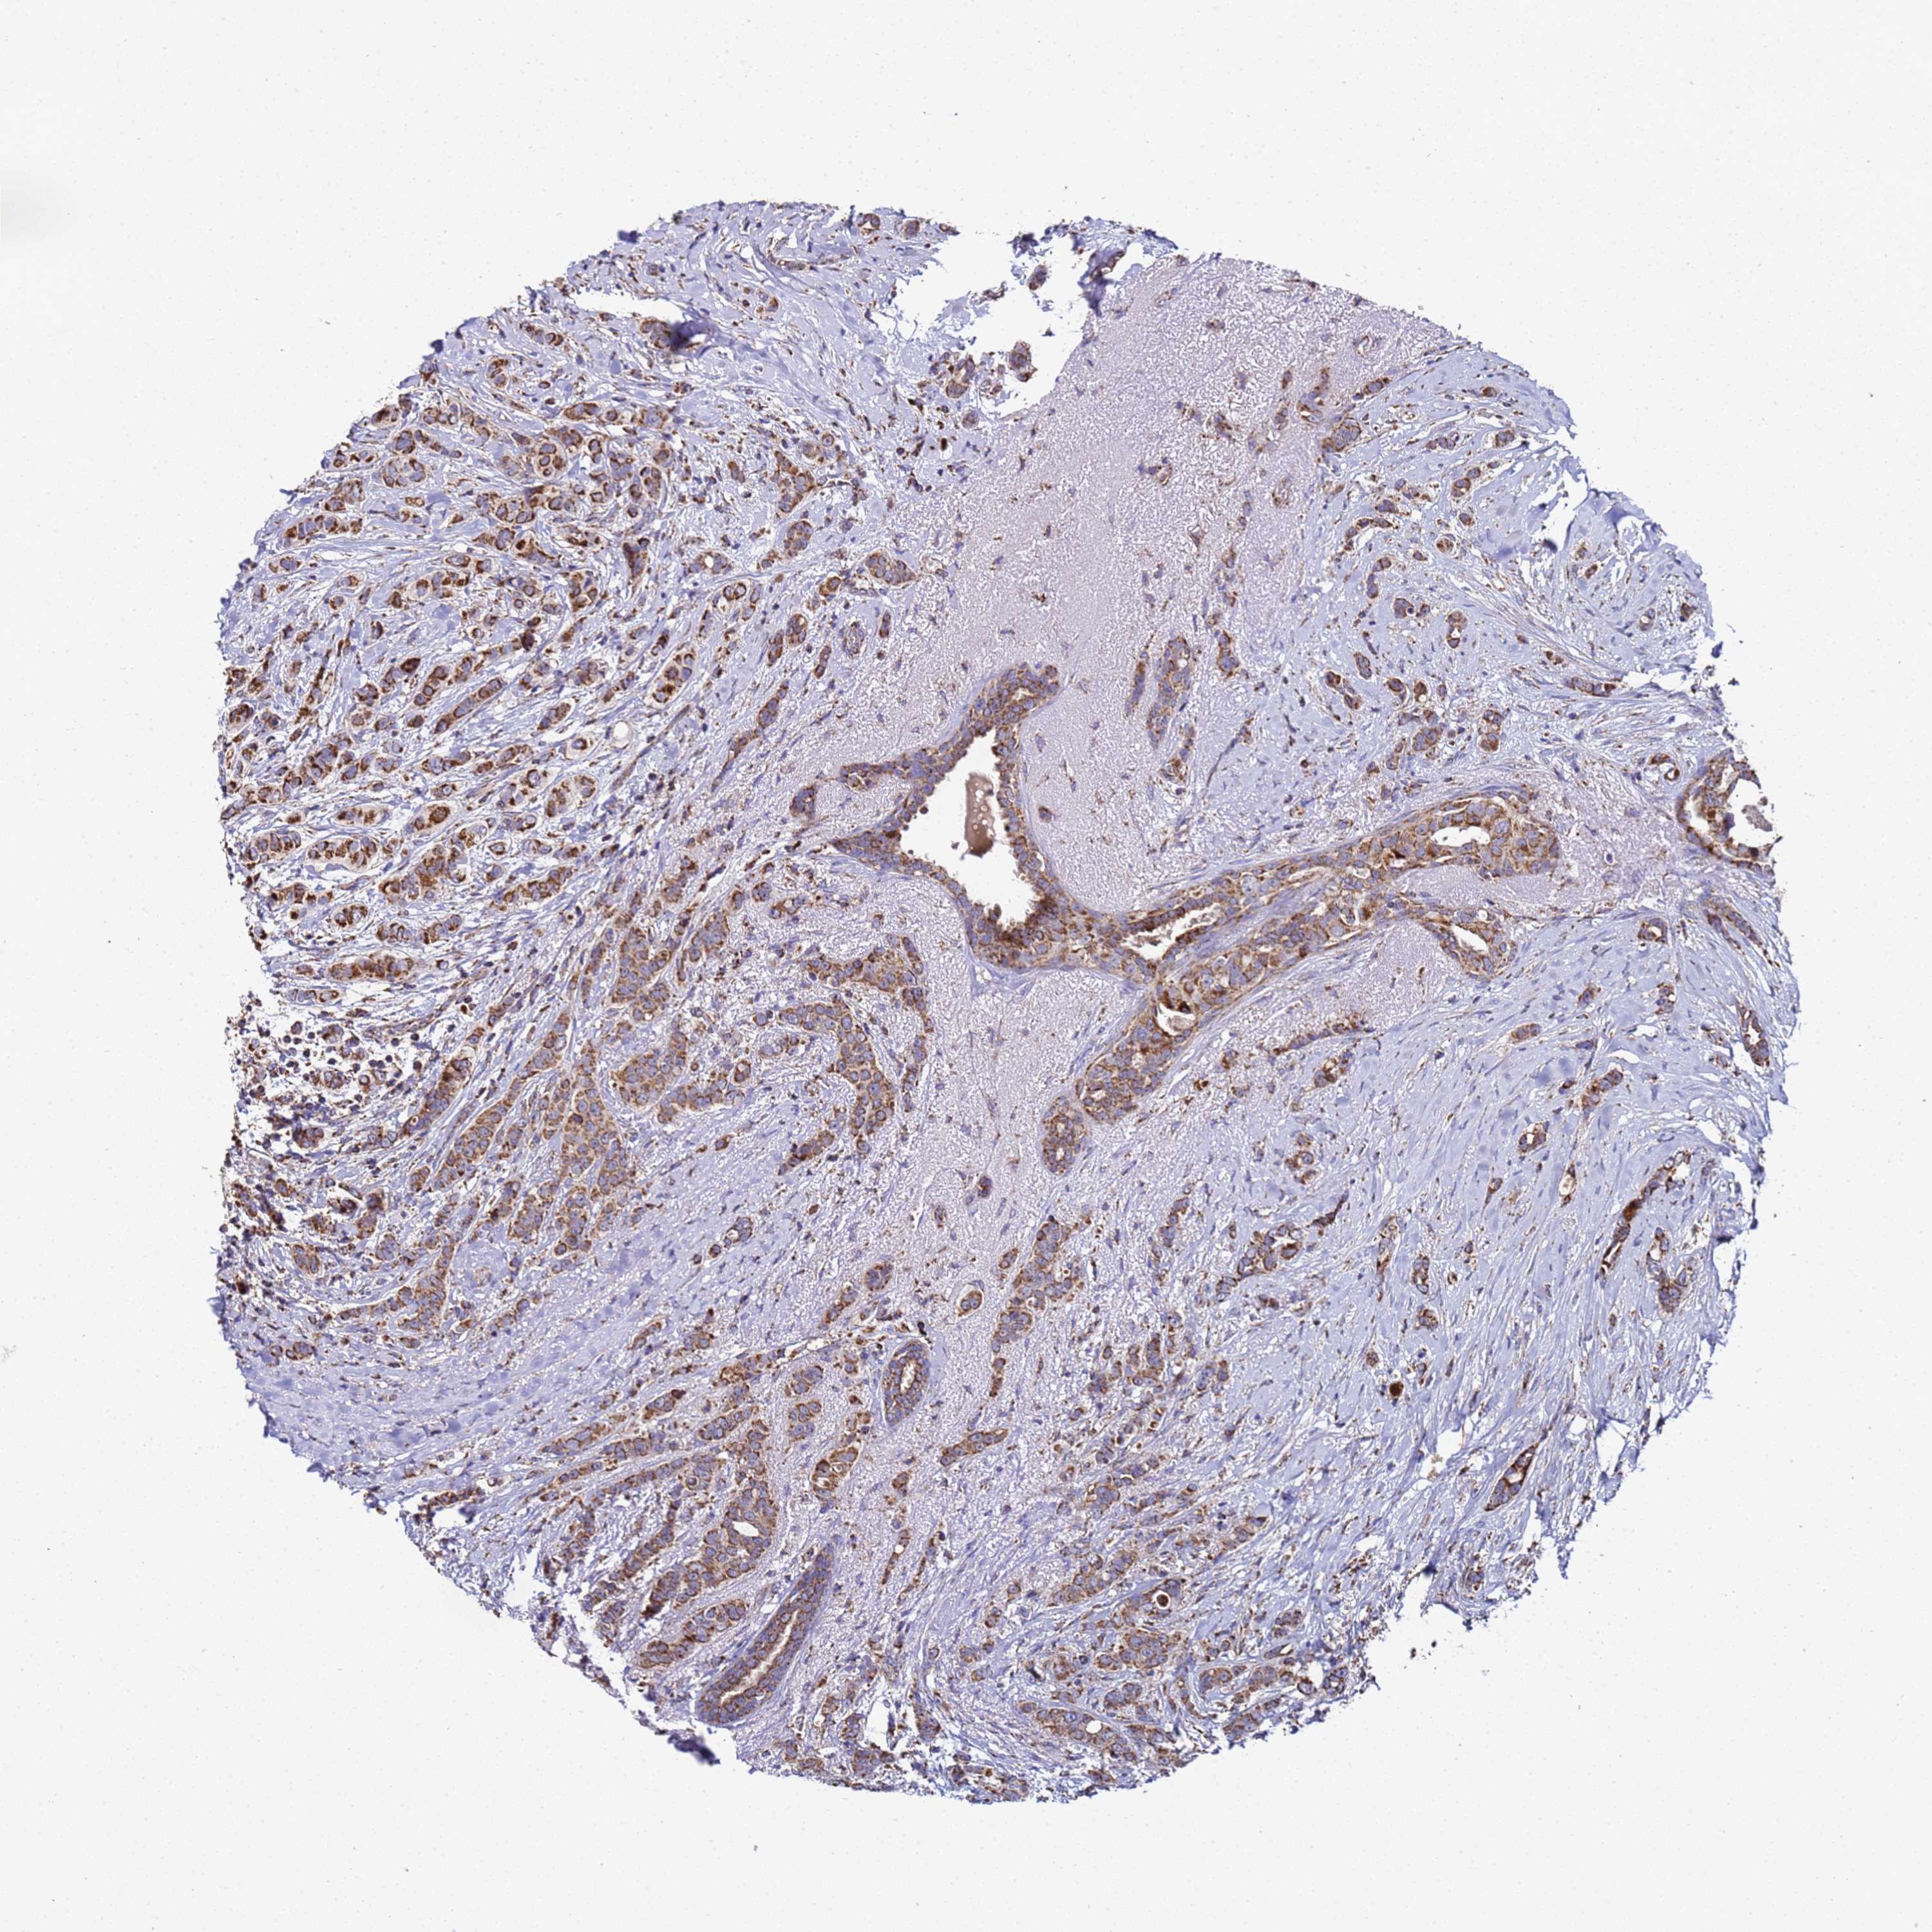

CANCER BREAST CANCER Show tissue menu

BRCA TCGA BRCA VALIDATION PROTEIN EXPRESSION

ANTIBODIES

AND

VALIDATION